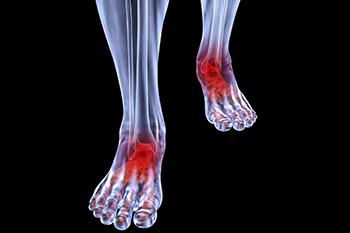

Conditions affecting the feet due to complications with arthritis can take many forms, including osteoarthritis, rheumatoid arthritis, gout, psoriatic arthritis, and ankylosing spondylitis. Osteoarthritis typically affects the joint connecting your big toe to your...